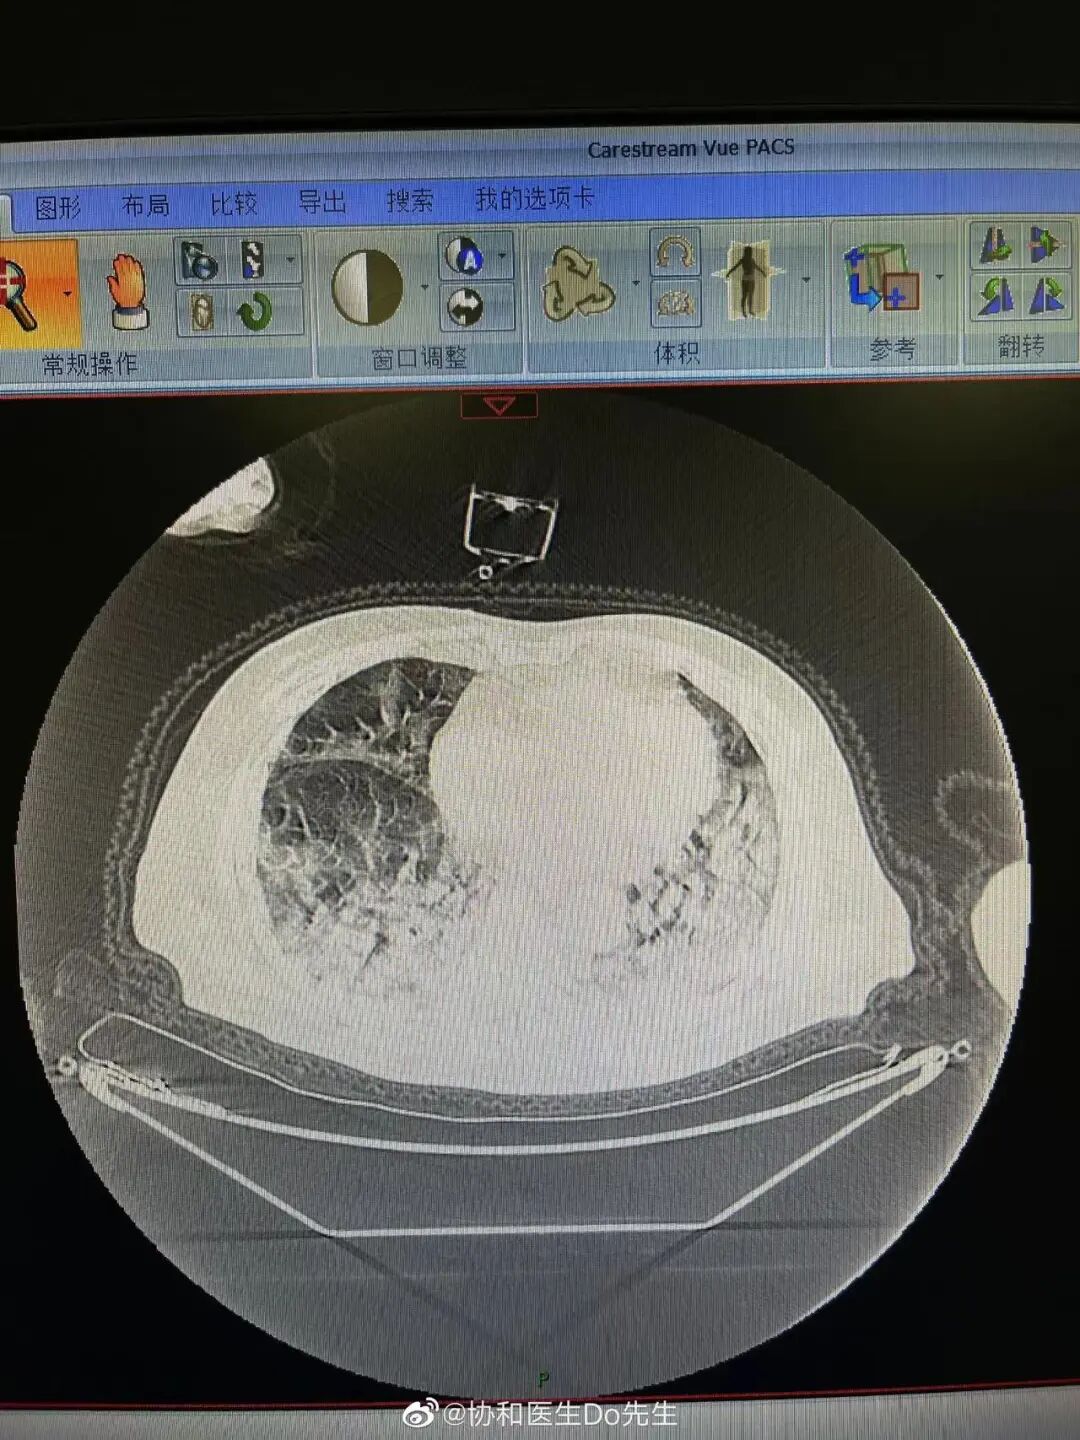

- 长沙8死5伤撞人案调查:案发前4小时与背后的拆迁..